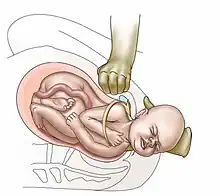

| Suprapubic pressure being used in a shoulder dystocia | |

- Anterior shoulder disimpaction (suprapubic pressure);[11]

- Suprapubic pressure (or Rubin I);[17]